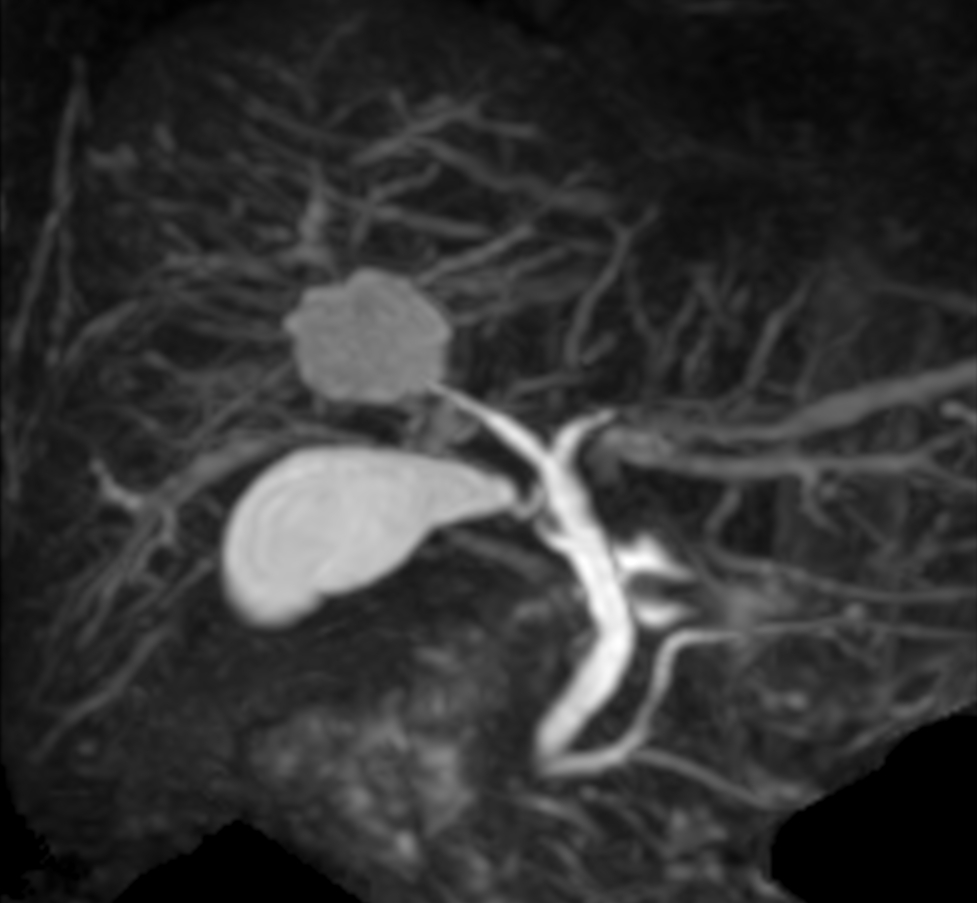

Coronal MRCP (GRASE, MIP)